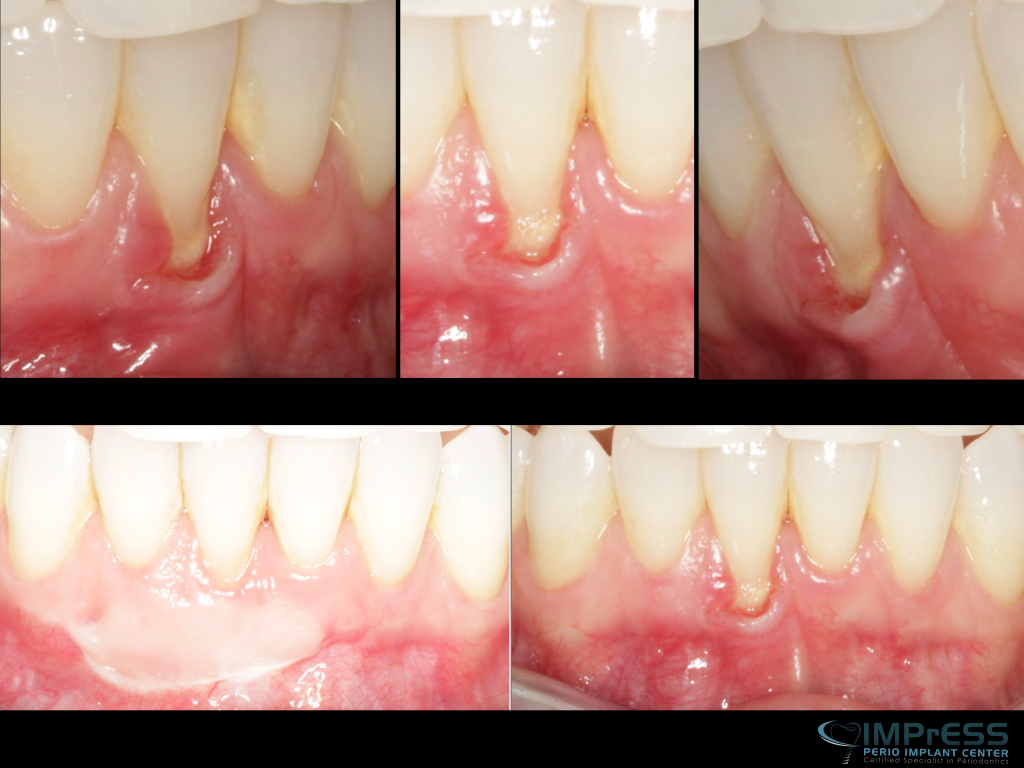

Connective Tissue Gingival Grafting for Gingival Recession